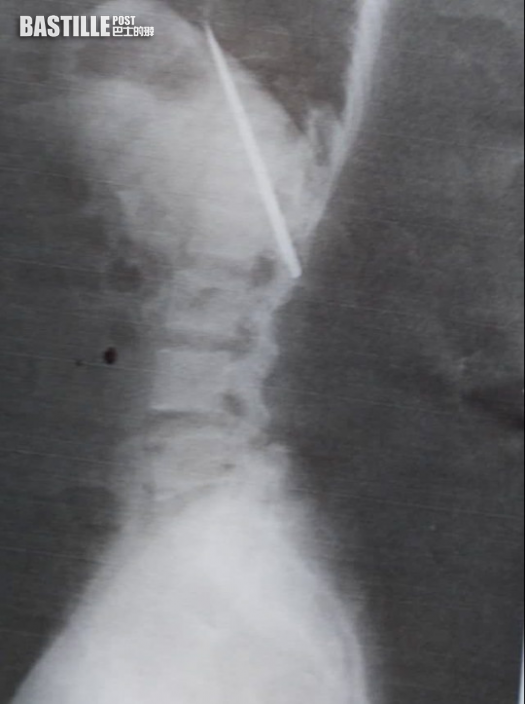

Tomao照X光時發現胸口埋有利刀已達14個月。(網上圖片)

Tomao於3月24日接受當地傳媒訪問,稱是照完X光才發現體內有刀刃,相信在體內已有14個月。他憶述去年1月時曾被一群少年持刀襲擊,估計刀刃是當時插進體內,「我當時以為中了一拳」。傳媒指他當時到醫院檢查,疑醫生及護士未有做詳細檢查,亦應沒有照X光,便告知Tomao傷口很淺,可直接縫合傷口,「我相信治療我的醫生」。

利刀位置靠近肺部。(網上圖片)